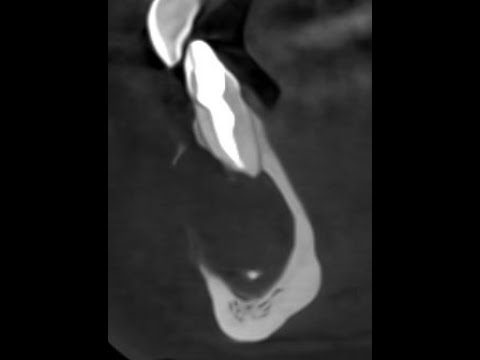

Можно ли жить с гранулемой зуба? Да, при этом можно достаточно долго не знать о ее существовании: часто она протекает бессимптомно и обнаруживается лишь на рентгене, который выполняется совершенно по другому поводу. Впрочем, ее можно предположить, если при нажатии на зуб или попадании твердой пищи появляется боль. Игнорировать это состояние не стоит, так как оно показывает, что в ротовой полости развивается воспалительное заболевание. Оно может привести к уменьшению объема кости, рассасыванию корней зубов и в конечном итоге — к потере зуба. Последствия запущенной гранулемы зуба могут быть и гораздо серьезнее: околочелюстной абсцесс, флегмона, остеомиелит челюсти. Чтобы не допустить этого, мы крайне рекомендуем ознакомиться с этим выпуском подкаста. А если вы не нашли ответ на свой вопрос в этом видео, то задавайте ваш вопрос в комментариях! 0:00 - О чем этот выпуск? 1:37 - Что такое гранулема зуба? 2:38 - Нужно ли лечить гранулему? 3:38 - Причины возникновения гранулемы 7:06 - Диагностика гранулемы 10:05 - Опасность гранулемы 12:32 - Самостоятельная диагностика гранулемы 15:40 - Гранулема в неживом зубе 17:40 - Гранулема у детей 18:36 - Хирургический метод лечения гранулемы 22:24 - Поэтапное лечение гранулемы 30:33 - ЛОР-стоматолог при лечении гранулемы 32:00 - Лечение гранулемы под седацией 36:30 - Установка коронки и винира на зуб с гранулемой #НачниУлыбаться #startsmile #Простоостоматологии #Стоматология Наши ресурсы: